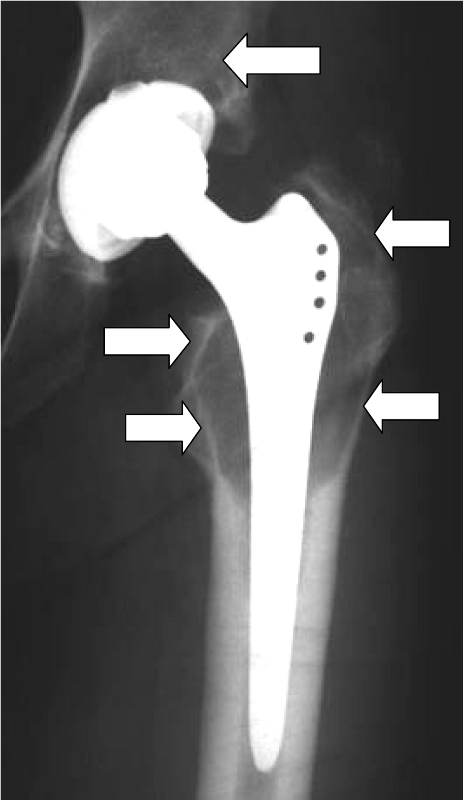

Although statistically only a small proportion of patients develop such hypersensitivity (the figures are less than 1% or between 1 and 4%, depending on the author), we attach great importance to the diagnosis and treatment of hypersensitivity reactions to prostheses in our hospital. If there is a proven allergy to prosthesis components, patients can be fitted with special prostheses made of titanium (hip) or implant coatings (knee). All-ceramic prostheses are currently still undergoing clinical trials. Before considering an implant allergy, however, other causes of the complaints, such as infections, mechanical problems or malpositioning, should be ruled out.

Beschichtete KnietotalendoprotheseDiffuse Lymphozyteninfiltration in der GelenkkapselOsteolyse um einen Prothesenschaft (Pfeile)